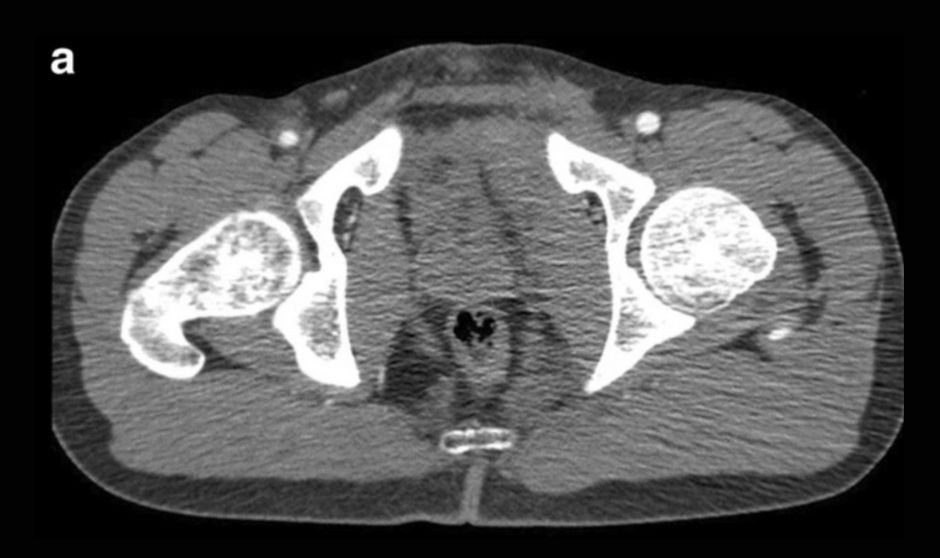

Imagen de pelvis.

Los expertos diagnosticaron las lesiones arteriales pélvicas en la angiografía por tomografía computarizada y añadieron una fase arterial a exploración de fase venosa portal más extendida. “Las lesiones arteriales se ven como extravasación en las imágenes arteriales o como hematomas en aumento en las imágenes tardías, mientras que las lesiones venosas carecerían de extravasación de contraste en la exploración arterial temprana”, señalan los investigadores

Los hallazgos positivos de la tomografía computarizada en la fase venosa de portal solo tuvieron una sensibilidad y especificidad del 62 por ciento y el 86 por ciento, frente al 56 por ciento y el 93 por ciento para los hallazgos simultáneos en la fase arterial y venosa portal.

La especificidad fue significativamente mayor para los hallazgos positivos en ambas fases en comparación con la fase venosa portal solamente. La aplicación de un umbral> 0,9 cm de diámetro de extravasación a la fase venosa portal sólo dio como resultado una sensibilidad y una especificidad idénticas a las de ambas fases.